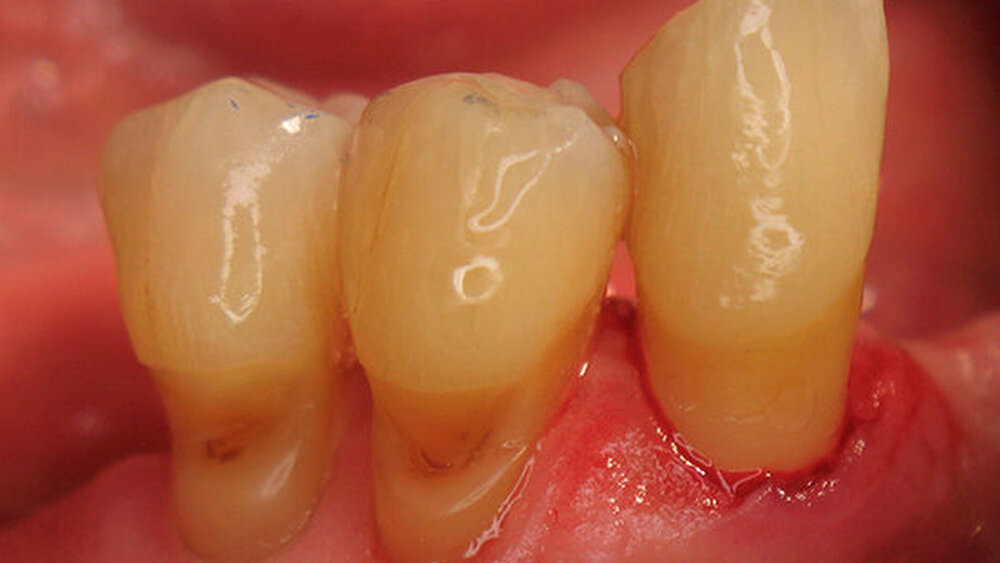

Der Patient (männlich, 72 Jahre alt) war vor der Behandlung bereits seit vielen Jahren parodontal erkrankt. Aufgrund der Einnahme verschiedener Medikamente litt er zudem unter Mundtrockenheit, so dass der Speichel seine wichtige Funktion als schützender Puffer für den Zahnschmelz nur ungenügend erfüllen konnte. Der Patient wies ausgeprägte Zahnhalsdefekte mit Rezessionen auf (Abb. 1-2) und reagierte nach der Parodontalbehandlung schmerzempfindlich auf Heißes, Kaltes oder Süßes. Zudem zeigten sich mehrere kariöse Läsionen.